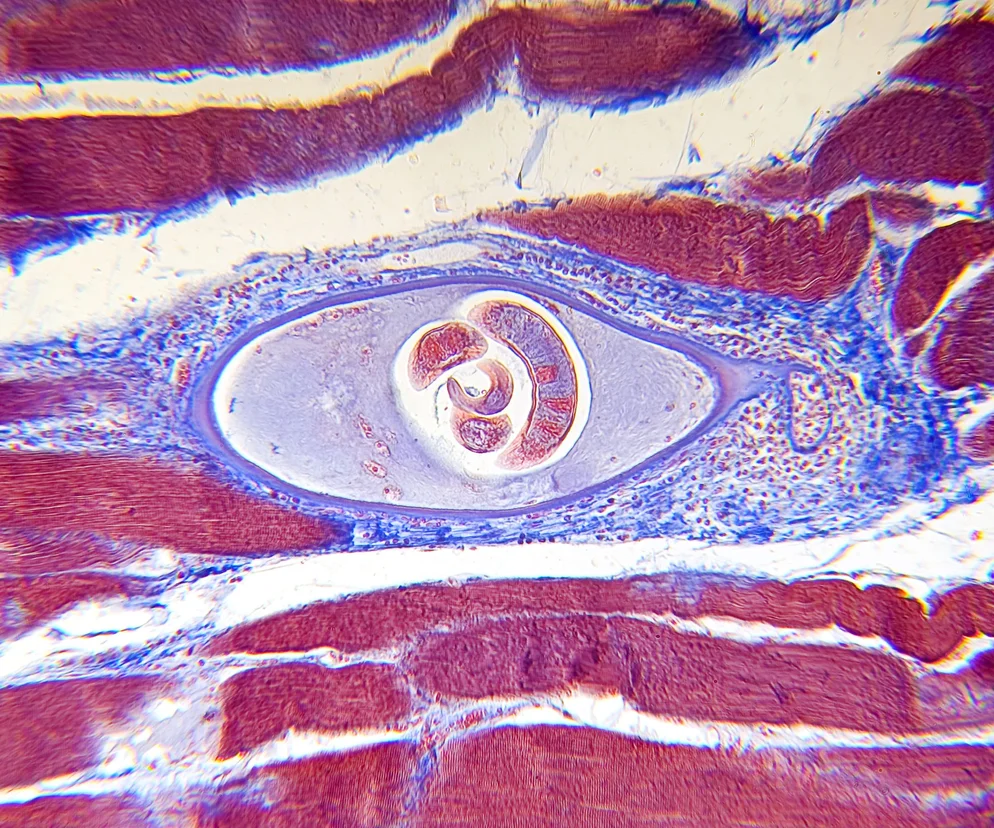

Włośnica (trychinoza, trichinelloza) to choroba pasożytnicza, wywoływana przez  włośnia krętego (Trichinella spiralis). Włośnicą można zarazić się, spożywając mięso zawierające larwy włośnia. Jakie są objawy włośnicy i jak przebiega leczenie? Jak uchronić się przed zarażeniem?

Jeśli mięso z cystami włośnia zostanie niewłaściwie przygotowane i spożyte, sok żołądkowy rozpuszcza otoczkę i larwa ma otwartą drogę do jelita cienkiego. Tam, po osiągnięciu dojrzałości płciowej w ciągu najbliższych 7-8 tygodni rodzą 1000-1500 żywych larw. To one właśnie przenikają przez ściany jelita i z krwią wędrują po całym organizmie, by po 12-15 dniach osiedlić się w mięśniach poprzecznie prążkowanych. Najczęściej wybierają mięśnie przepony, ale znajduje się je również w mięśniach międzyżebrowych, języku, krtani, mięśniach grzbietu. Po osiedleniu się otorbiają się, tworząc tzw. wągry, których otoczka ulega z czasem zwapnieniu. W tej postaci, odizolowane od organizmu, larwy mogą przeżyć w organizmie człowieka nawet 20–40 lat.